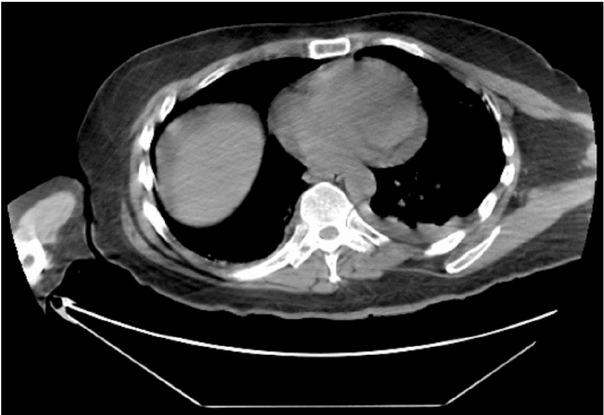

Fig. 1